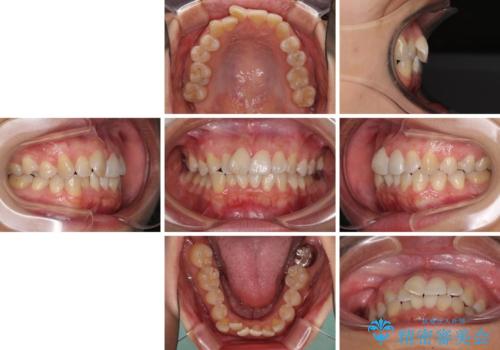

前歯のデコボコをインビザラインでスッキリと仕上げる

- 上下前歯のデコボコと奥歯の銀歯を気にして来院された患者様です。

口元をインビザラインにより歯列を整え、その後に失活している奥歯をオールセラミッククラウンにて補綴治療することとしました。

長時間のマウスピース装着に協力いただき、自然な口元に仕上げることができました。

気になっていた銀歯もオールセラミッククラウンで本物の歯のようになり、患者様には大変満足していただきました。